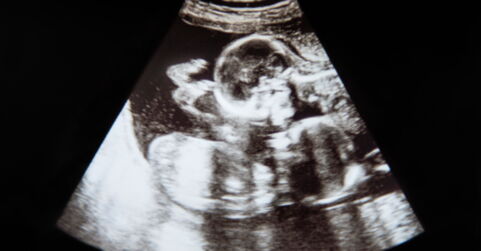

After undergoing a scan, doctors discovered something quite strange. The lump in her stomach was caused by bits of bone that looked like a spine and ribs. It didn’t take long for the experts to realise what it was. Doctors diagnosed the teenager with the foetus in the foetus, an embryonic anomaly that is caused when a foetus starts to develop inside their twin.This rare medical anomaly only occurs in 1 in 500,000 live births in the world and generally occurs quite early on in pregnancy.

The foetus was removed during a surgical procedure and according to the doctors, the lump was two-thirds the size of a full-term baby. Not all of the matter was able to be removed, however, since some of the tissue had adhered too closely to her blood vessels. But by leaving this tissue in her stomach, there is a chance it could become cancerous. However, it has been 2 years since she had the operation and the young woman hasn’t had any significant issues.